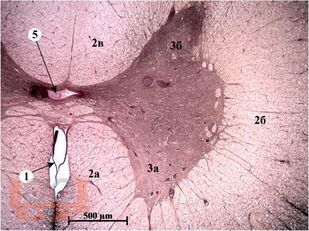

Учебное пособие состоит из оригинальных цветных фотографий, каждая из которых сопровождается описанием и указанием учебных элементов.